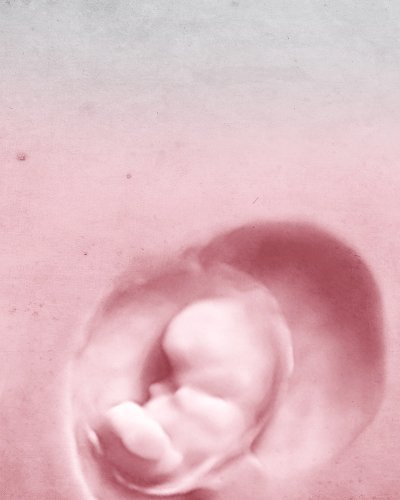

Ayudamos a formar su familia

ESTUDIO DE FERTILIDAD PERSONALIZADO

PARA INDIVIDUALIZAR EL TRATAMIENTO